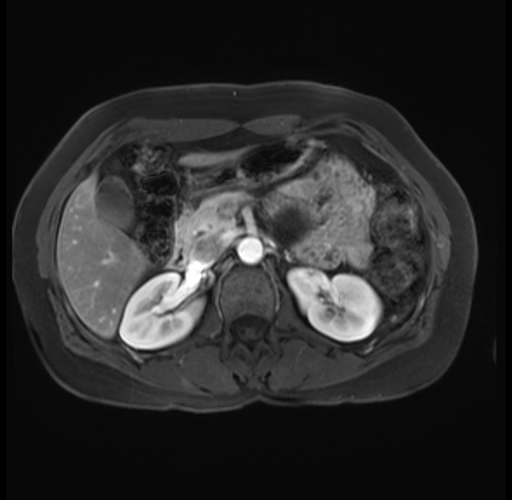

Imaging Analysis

Look through the patient's CT scan to identify any areas of concern for the necessary procedure.

Based on your CT findings, which issue(s) are present and would give reason for "planned slowing down moment(s)" in this case?

Considering a standard distal pancreatectomy procedure, what step(s) of the operation would you do differently in this case?